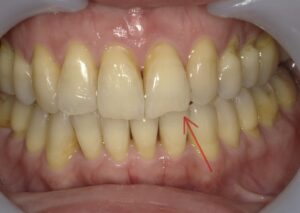

【症例2】50代・矯正は難しいと言われ半ば諦めていたガタガタの改善

「数カ所の歯科医院で相談をしたが、矯正が難しいと言われ諦めかけていた」という50代女性のケースです。前歯が元々欠損しているため真ん中を合わせることはできませんが、ガタガタはIPRや側方拡大を行い治すことができました。

仕上げに前歯のすり減りをダイレクトボンディングで直し、より整った印象にしています。

- 治療方法: ワイヤー矯正上下

- 治療期間: 12ヶ月

- 治療費用: 77万円(税込)

- 治療のリスク・デメリット:ブラックトライアングル

- ポイント: 比較的短期間のプランで、前歯の見た目と清掃性を大幅に向上させました。